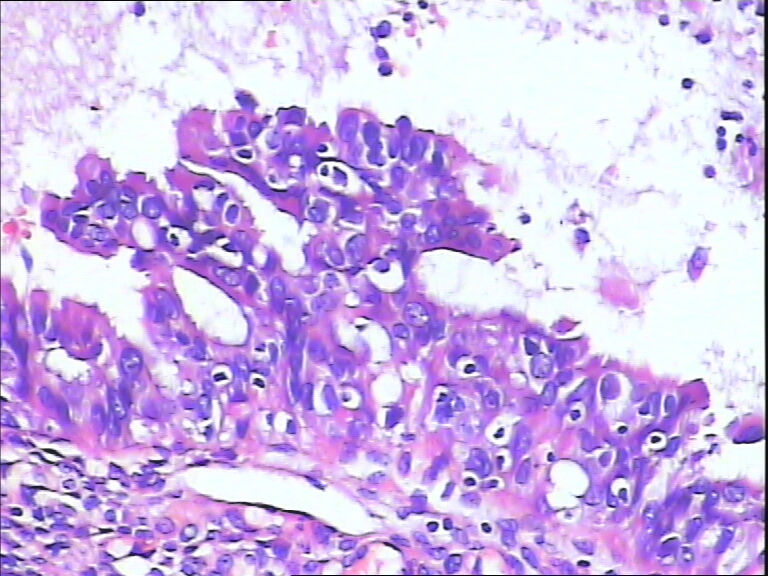

女,43y

左输卵管积液

输卵管长4.5cm;直径:0.8cm

输卵管增生性上皮病变。

慢性炎伴上皮增生

良性,炎症改变

考虑炎症